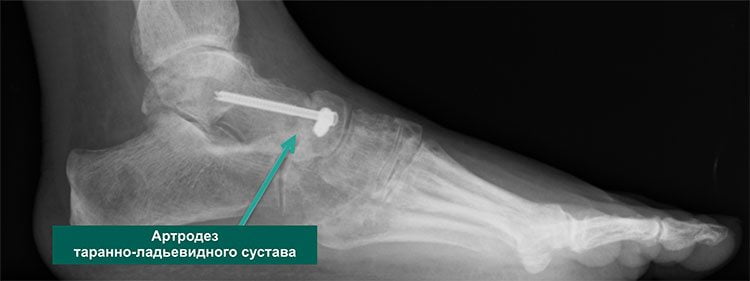

Хирургия

Если консервативная медицина остается бессильной перед артрозом таранно-пяточного сустава, то больному приходится соглашаться на хирургическую операцию. Этот вид лечения показан при заболевании последней стадии, когда дистрофия сочленения стала необратимой. Решение о проведении операции принимает врач.

Хирургическое лечение позволяет получить хорошие результаты: устраняет боль и возвращает пациента к обычной повседневной жизни. Суть оперативного вмешательства состоит в удалении из сустава всех поврежденных дистрофией фрагментов и создании благоприятных условий для его последующего сращивания. Операция проводится под общим наркозом.

Многих пациентов пугает мысль, что стопа после хирургического вмешательства будет полностью обездвижена. Но вопреки всем страхам при правильном восстановлении человек, страдающий много лет артрозом, сможет полноценно жить, заниматься спортом, вести активный образ жизни без боли и практически без хромоты.

Осложнением операции может стать формирование ложного сочленения. Такое возникает тогда, когда кости друг с другом не срастаются. Потребуется повторная операция с дополнительной костной пластикой для быстрого заживления.